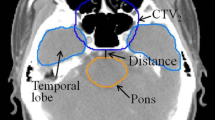

5 set-up uncertainties were introduced on the original VMAT plan, shifting the isocenter from its reference position according to the set-up errors acquired by CBCT. The U-plans, representing the perturbed plans introduced set-up uncertainties, were calculated for 33 fractions to facilitate the dose comparison. The evaluated items of PTVs and OARs were listed in Table 2 (Fig. 1).

Figure 2 shows a schematic of transversal dose distributions in 1 treatment plan and 5 U-plans. The transversal dose coverage varies due to set-up uncertainty. To visualize the dose difference, a color wash schematic of differences in dose distributions is shown in Fig. 3. The maximum dose discrepancies were observed in marginal zones of PTVs. The dose changes of OARs were also greater in the vicinity of marginal zones and lesser distal to these areas.

The average dose difference was shown in Table 3. No obvious differences were found in D2cc. The mean dose differences of D98% and D95% of PTVp were respectively 3.30 Gy and 2.02 Gy. Decreased ΔD98% (1.12 Gy) and ΔD95% (0.58 Gy) were seen in CTVp. The ΔD98% and ΔD95% in GTVp were 0.56 Gy and 0.33 Gy, indicating that the CTV-to-PTV margin promoted the robustness of GTV and CTV. Similarly, the PTVn had the largest difference of D98% (2.77 Gy) and D95% (2.00 Gy). The ΔD98% and ΔD95% of CTVn were 1.39 Gy and1.03 Gy. Minor dose differences were observed in GTVn for both D98% (0.64 Gy) and D95% (0.59 Gy). No marked mean dose variations of Dmean were seen. Superior robustness in PTV and CTV was seen.